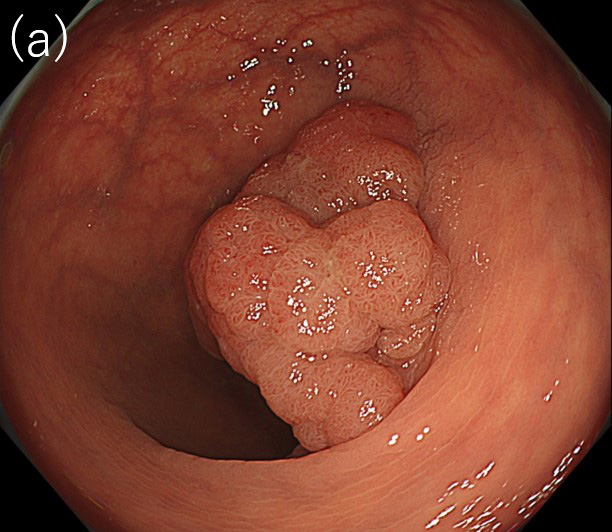

〈図3〉 XZ1200による30mm大Is+IIa(LST-G)病変

(病理診断:Adenocarcinoma, tub1, in tubular adenoma, pTis, Ly0, V0)に対する観察像

(a)白色光中遠景観察像